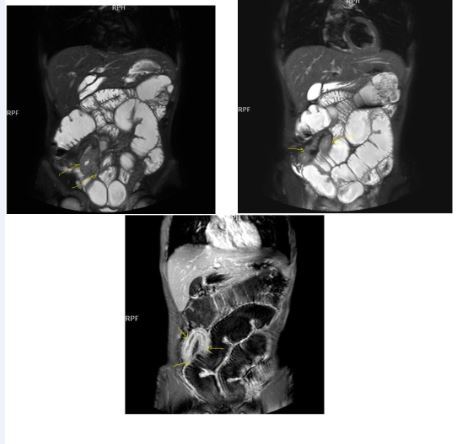

Bowel wall thickening with increased luminal and extra-luminal signal changes on FS images, showing active inflammation, edema in the adjacent intraperitoneal and mesenteric spaces, active inflammation; bowel wall thickening and enhancement on post-contrast T1W images plus high signal intensity on T2W- FS images7, 9, 12, 14, 17, 18, 19, 20, 21 (Figure 4a-b).

Chronic disease without active inflammation; Bowel wall thickening and enhancement on postgadolinium T1W images plus low signal intensity on T2W-FS images with possible stenosis and obstruction due to fibrosis, chronic disease with active inflammatoryexacerbations;these conditions can overlap with active inflammation, require longitudinal repeated scanning7, 12, 14, 20,26, 27, 28, 29, 30 (Figure 5a-b, Figure 6a-b)

Figure 4a.Mucosal involvement and lack of opacified ileal segments with loss of intestinal folds and increased bowel wall thickness due to Crohn’s disease on T2W coronal sequence after OCA, presented at 37 years old male with moderate Crohn’s disease.

Figure 4b.Mucosal, luminal and bowel wall involvement in Crohn’s disease with skipped lesions, seen at T2W axial image after OCA, presented at 45 years old male with severe inflammatory disease.

Figure 5a.Enhancing bowel segments due to Crohn’s disease, on T1W post-contrast axial image, luminal enhancement is predominant, shown at 62 years old female with mild disease status.

Figure 5b.İrregular bowel wall and luminal enhancement of ileum, with loss of valvula conniventes on T1W coronal post-contrast sequence, seen on 26 years old male with moderate inflammatory bowel disease.

Figure 6a.Diffuse homogeneous contrast enhancement on the bowel wall and mucosa due to Crohn’s disease, seen at T1W post-contrast axial image, indicated at 23 years old male with mild disease status.

Figure 6b.Heterogeneous bowel wall and mucosa involvement with collaborating skip lesions, specific for Crohn’s disease, predominant in ileum and terminal ileum which are shown at T2W coronal sequence after OCA, regarded at 39 years old female with severe disease.